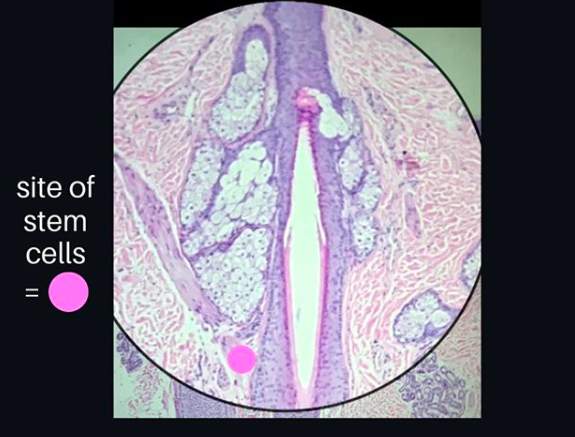

The Bulge: The Location of Follicular Stem Cells

The Hair Follicle Bulge

Hair follicle stem cells are cells with the potential to generate new hairs and potentially even other tissue types as well. There is an incredibly important area of the hair follicle where stem cells live. This area is known as the “bulge” and is located where the arrector pili muscle inserts into the outer root sheath (see pink dot in diagram). It was Dr George Cotsarelis, together with Dr Robert Lavker who discovered back in 1990 that the bulge was the location where hair follicle stem cells reside. Dr Cotsarelis was a dermatology resident at the time he made these breakthrough discoveries. He has since contributed to some of the most important discoveries in hair research in recent times.